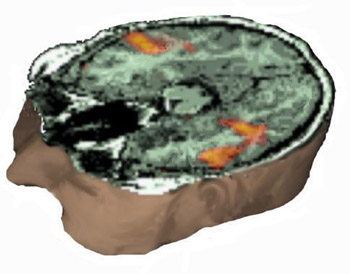

Case 2

17 year-old right handed boy with intractable epilepsy of partial motor type. MRI showed signal abnormality in the left middle frontal gyrus consistent with cortical dysplasia.

MRI of the head with partial exposure of the brain and skull. An axial view located at the superior third of the inferior frontal gyrus demonstrates in red the activation obtained with a verb generation task. The yellow spot represents the lesion and is derived from a fluid attenuated inversion recovery (FLAIR) sequence, and rendered with the rest of images, revealing the relationship between the lesion and the eloquent areas.